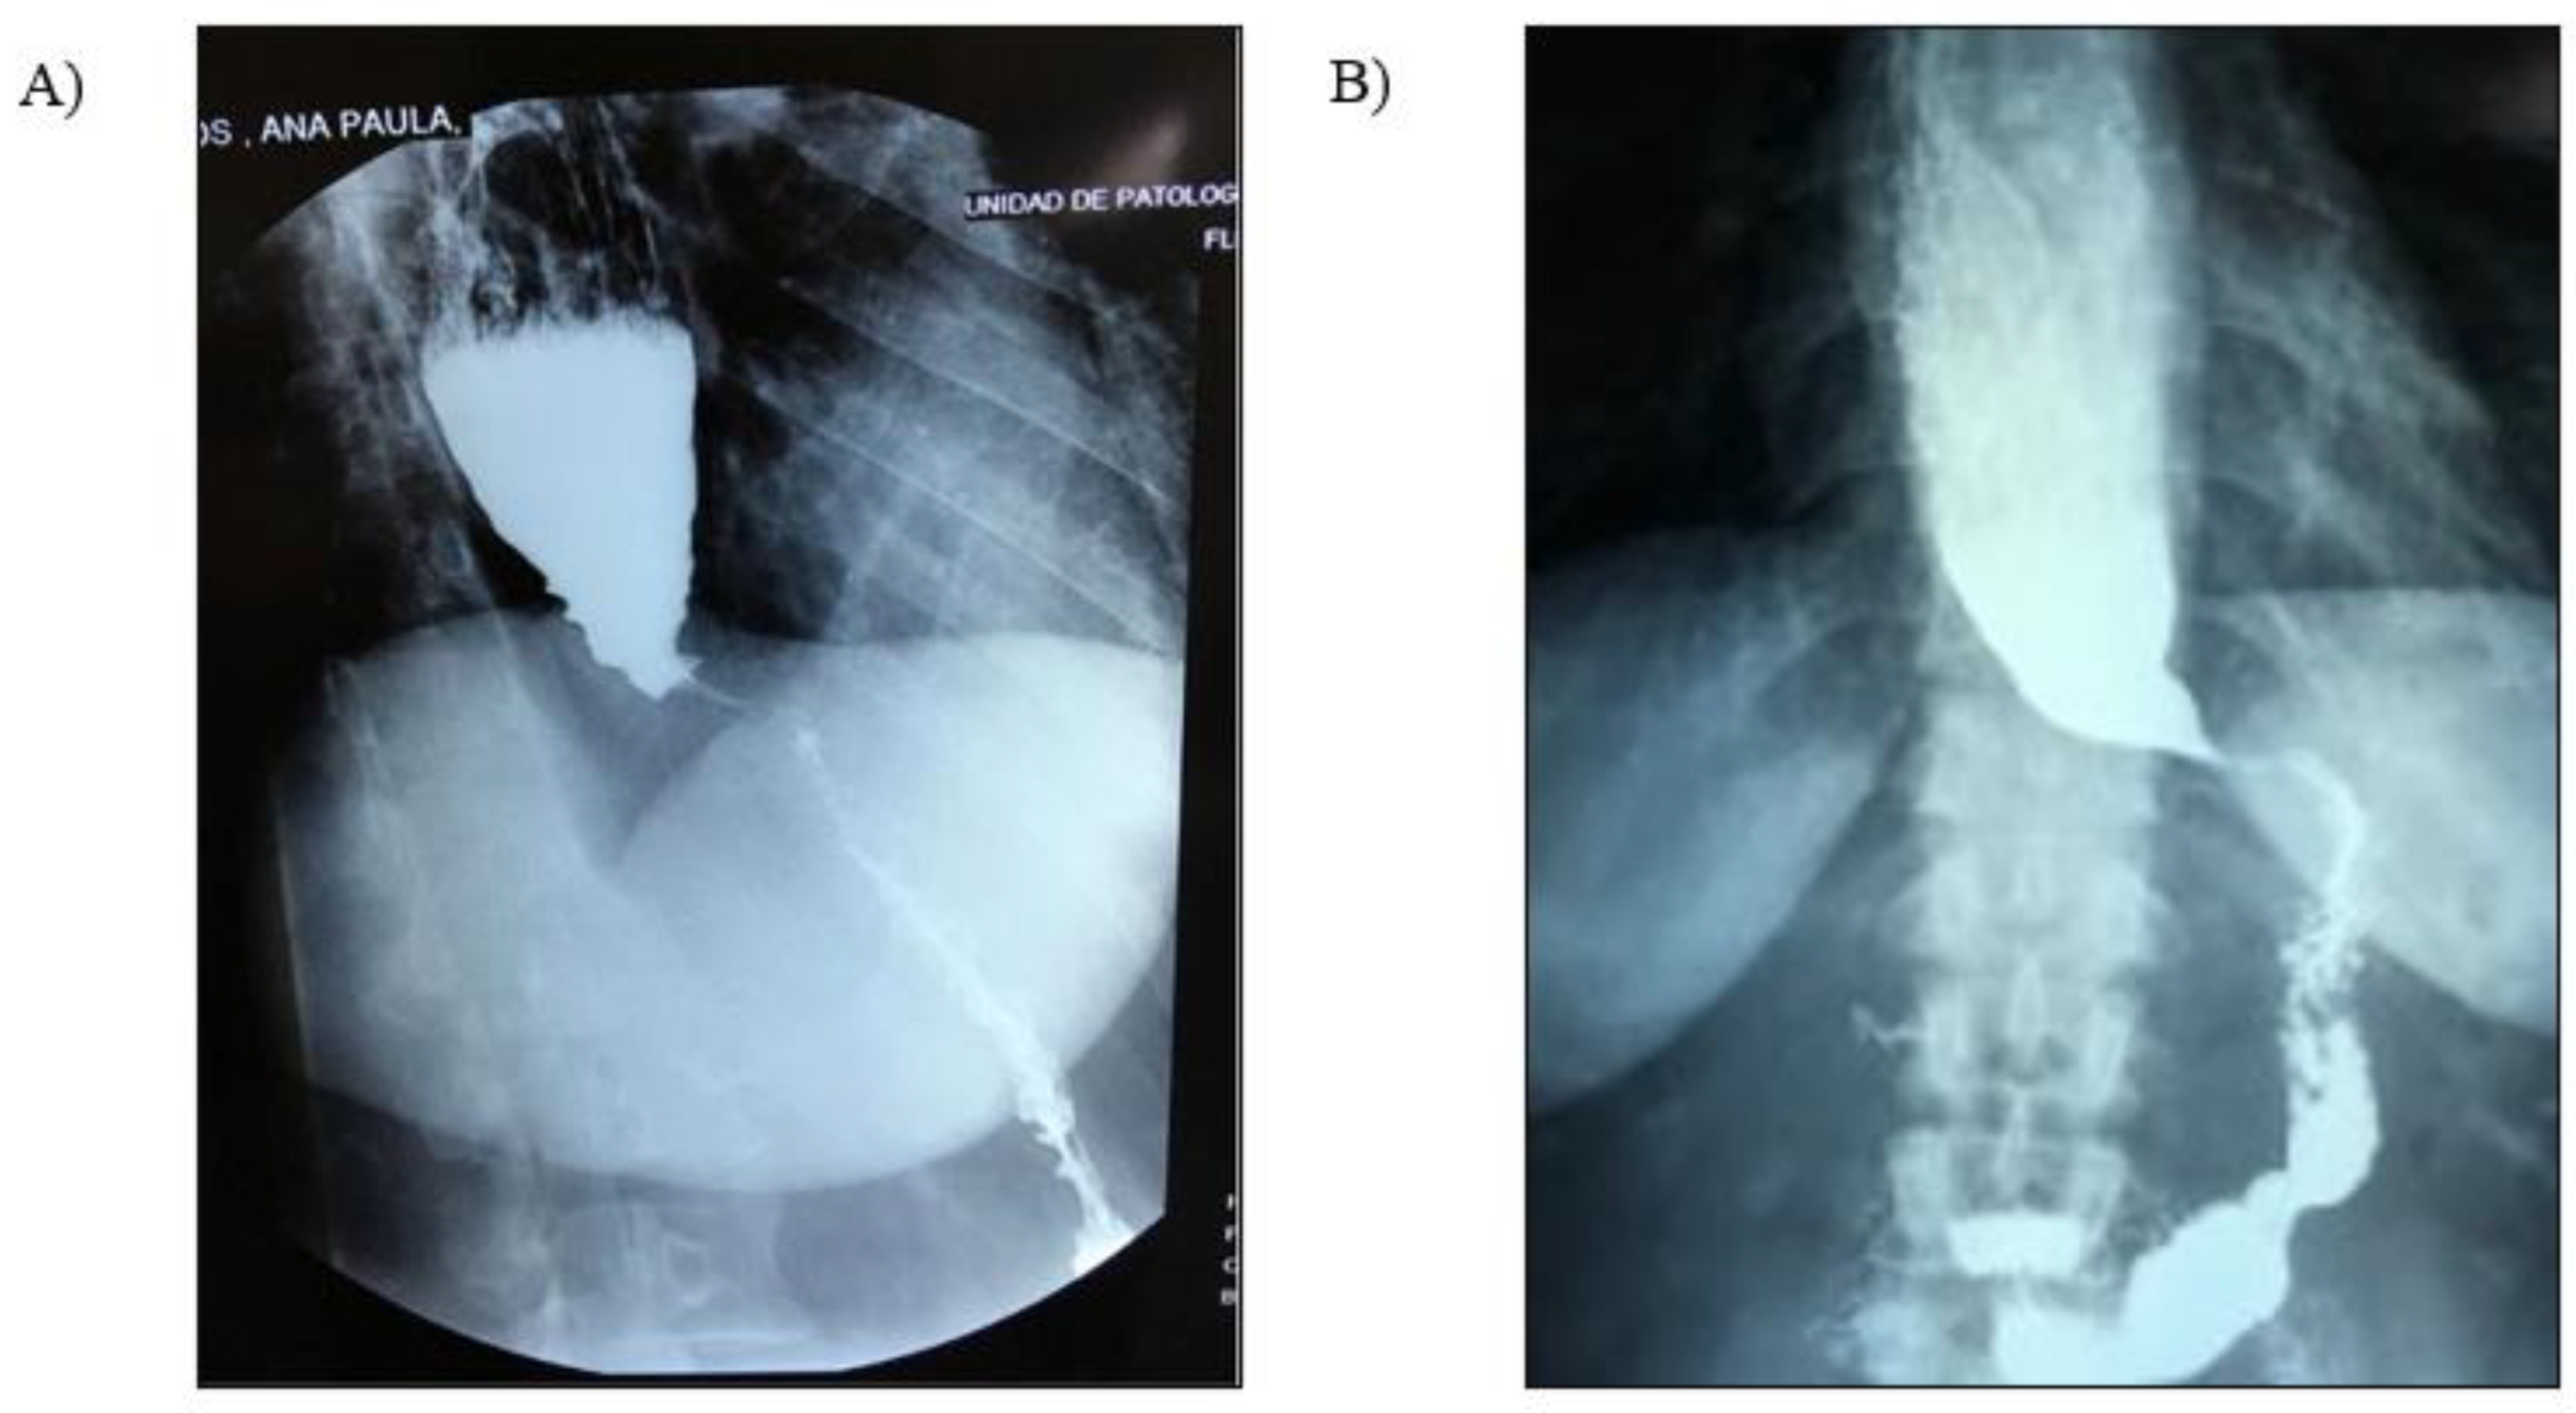

2. Case Presentation